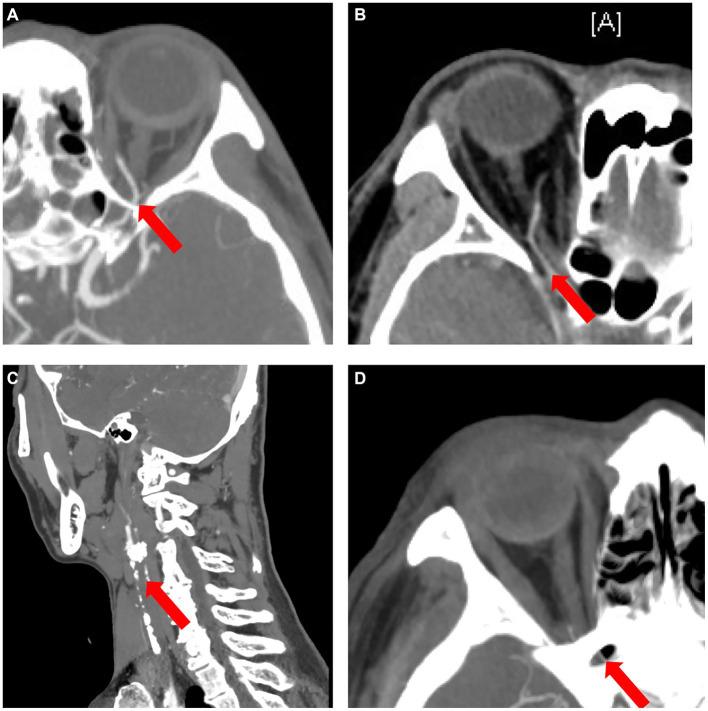

By observing and comparing the morphological and functional differences of the ophthalmic artery (OA) in patients with ocular vascular accidents (OVAs) due to iatrogenic embolism or non-iatrogenic occlusion, we propose a classification system based on the characteristics of OA on invasive digital subtraction angiography (DSA).

A total of 27 eyes of 27 patients were included in this study. Based on the results of carotid/intracranial arterial DSA, the morphological and functional abnormalities of OA with OVAs can be divided into five types. The proportion of males (7.14%), ocular ischemic syndrome (OIS) (0.00%) and neovascular glaucoma (NVG) (0.00%) in the iatrogenic embolism category was significantly lower than that (84.62, 61.54, and 69.23%, respectively) of the non-iatrogenic occlusion category ( < 0.001,  = 0.001,  < 0.001, respectively). However, the proportion of no light perception (NLP) (100%), anterior segment ischemia (ASI) (71.43%), and orbital involvement (ophthalmoplegia and ptosis, 42.86%) eventually occurring in the former was significantly greater than that in the latter (23.08, 0.00, 0.00%, respectively) ( < 0.001,  < 0.001,  = 0.010, respectively).

Ocular vascular accidents can be divided into five types based on the characteristics of OA on DSA.